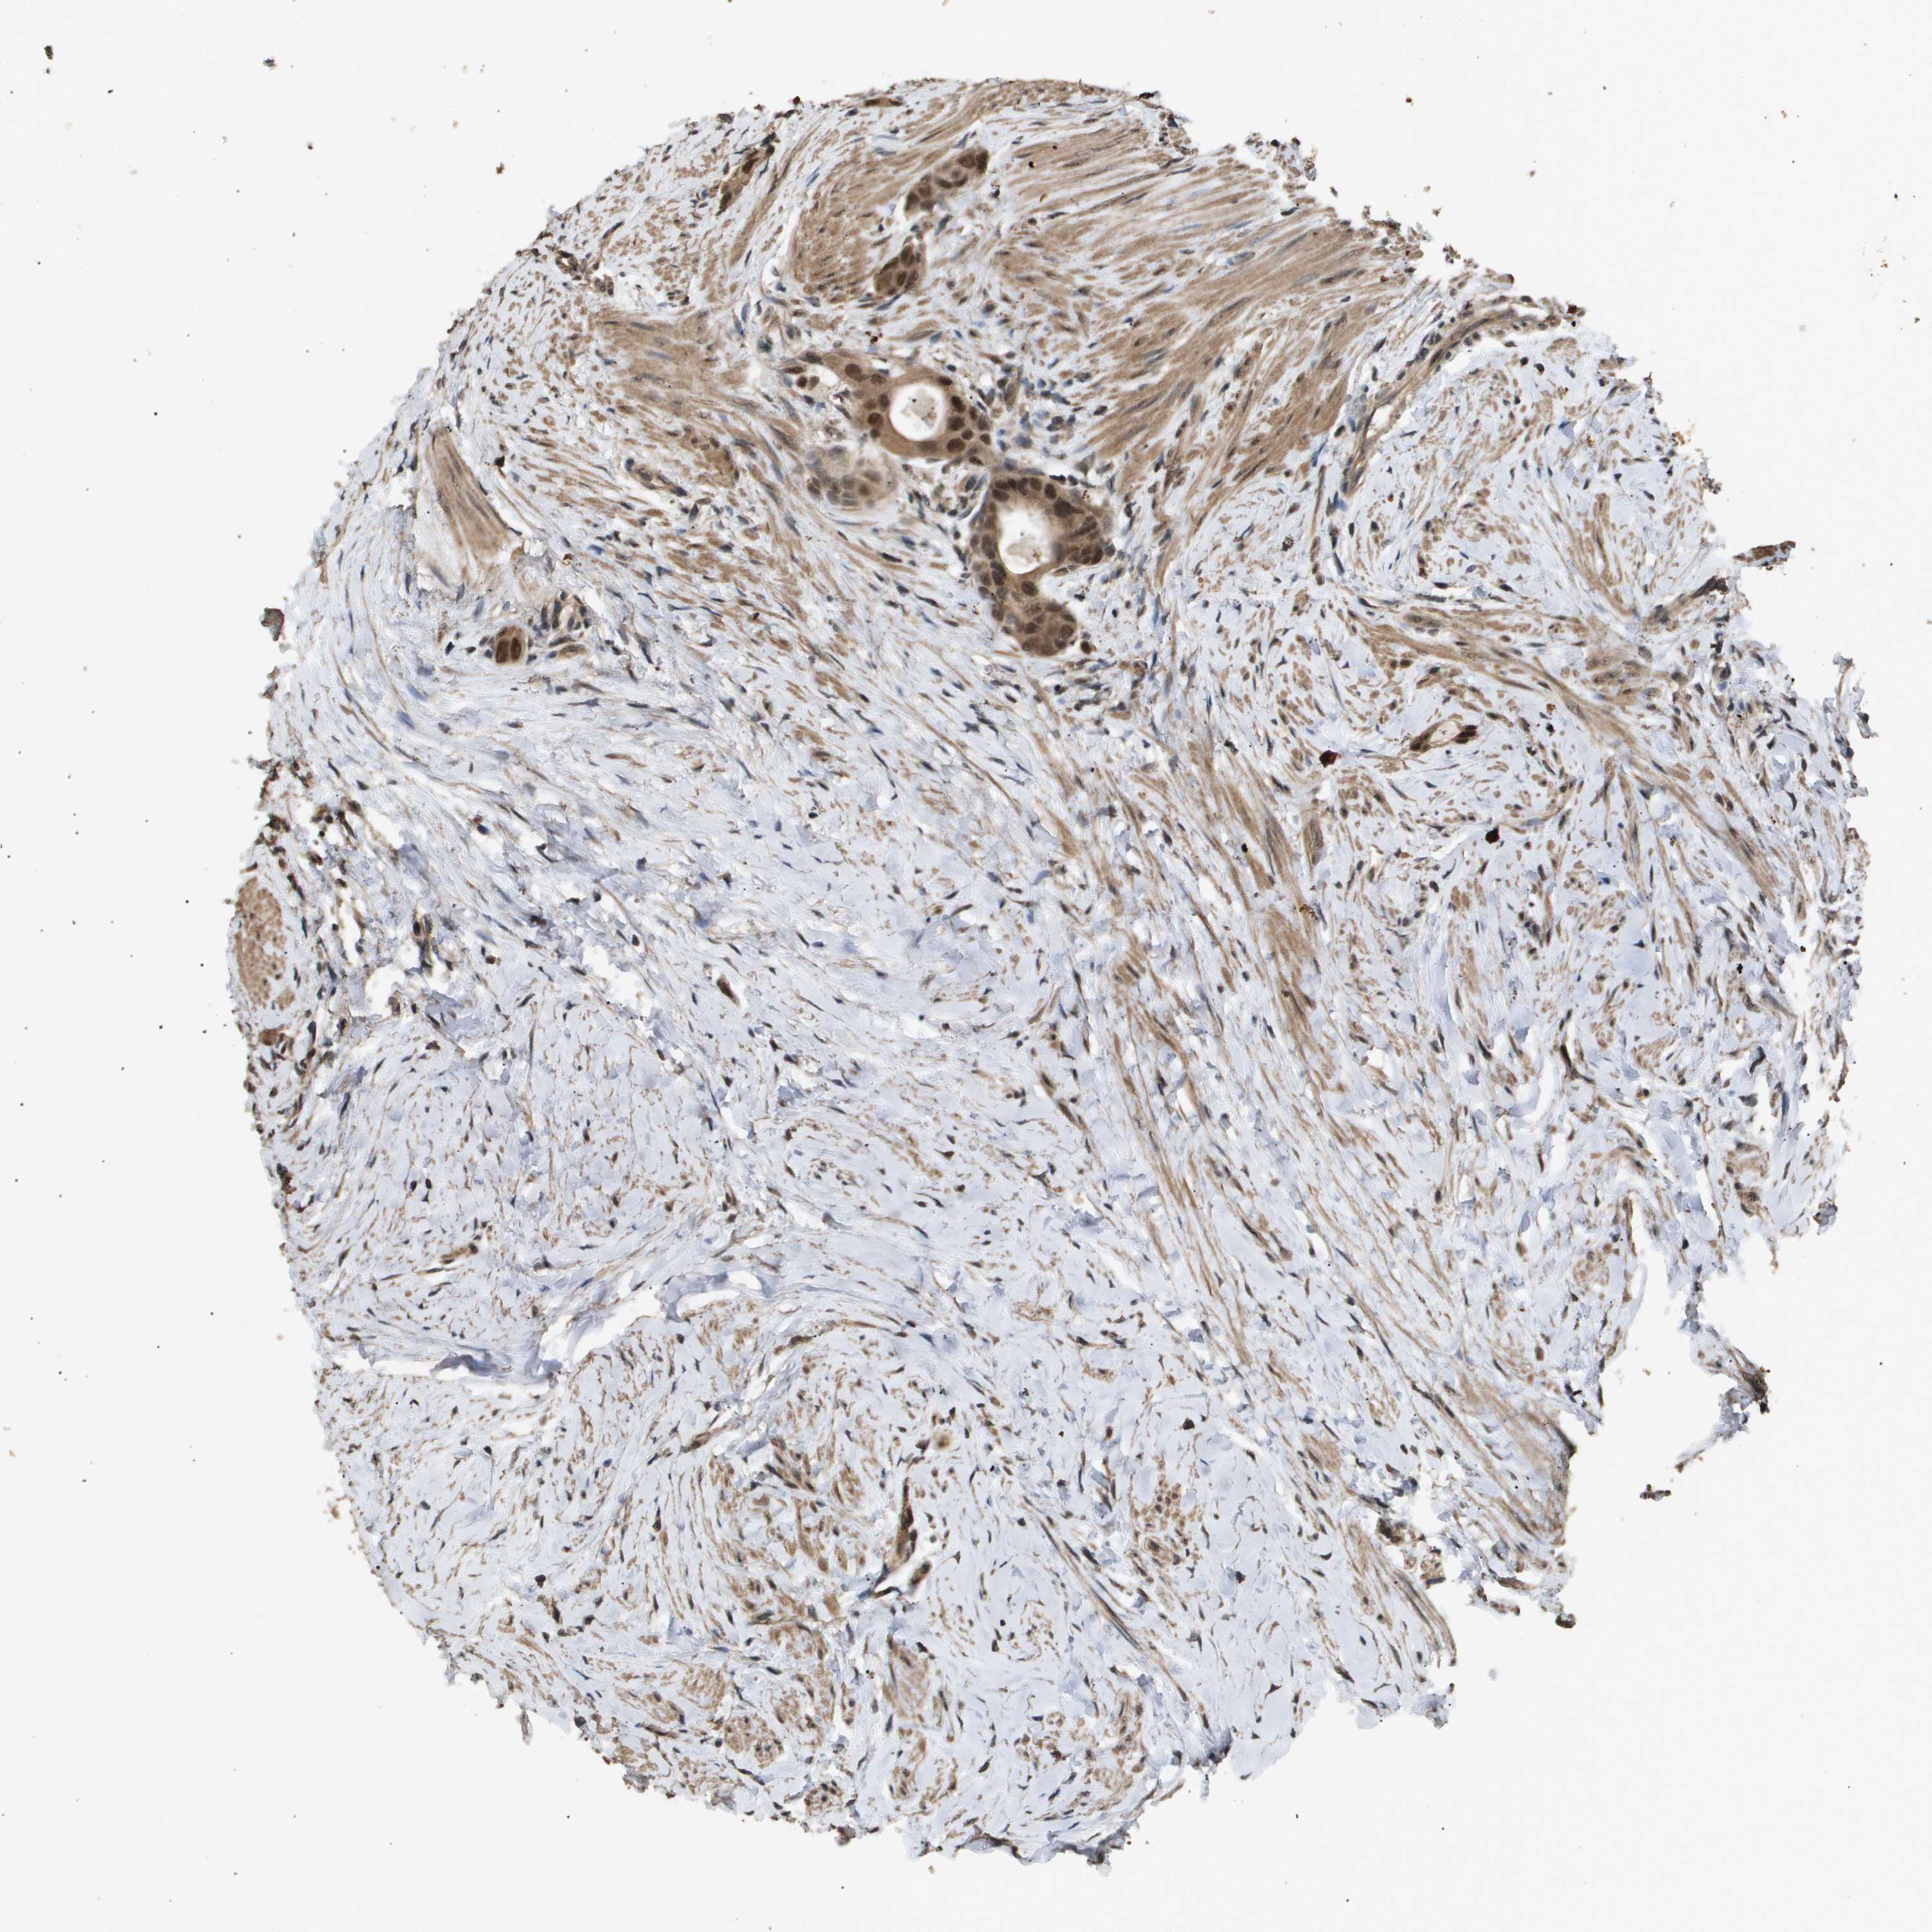

CANCER COLORECTAL CANCER Show tissue menu

COAD TCGA COAD VALIDATION READ TCGA READ VALIDATION PROTEIN COAD CPTAC PROTEIN EXPRESSION

ANTIBODIES

AND

VALIDATION